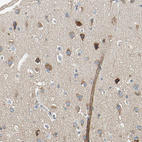

Immunohistochemical staining of human colorectal cancer shows strong cytoplasmic positivity in tumor cells.